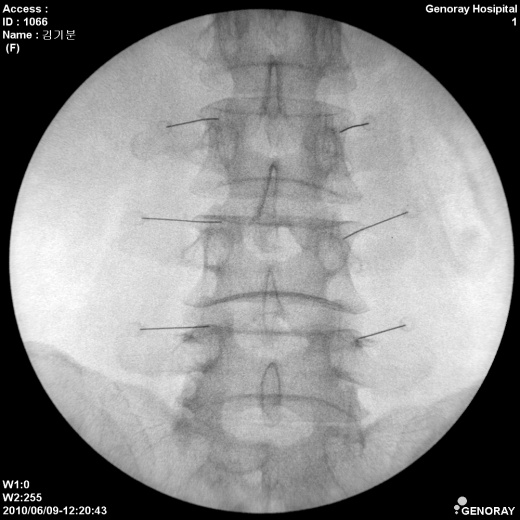

Аппарат применяется в различных областях медицины, таких как хирургия, ортопедия, педиатрия, травматология, урология и многих других. «АРХМ-РЕНЕКС» имеет широкий диапазон перемещений, легко позиционируется во всех направлениях, а так же имеет не большие габариты и вес обеспечивающие маневренность и простоту перемещений.

В качестве приемника используется усилитель рентгеновского изображения (УРИ) с ПЗС-матрицей 1024х1024 пикселей. Мощность рентгеновского питающего устройства 2,2 кВт.

- Непрерывная и импульсная рентгеноскопия с цифровой обработкой изображения.

- Цифровая рентгенография.